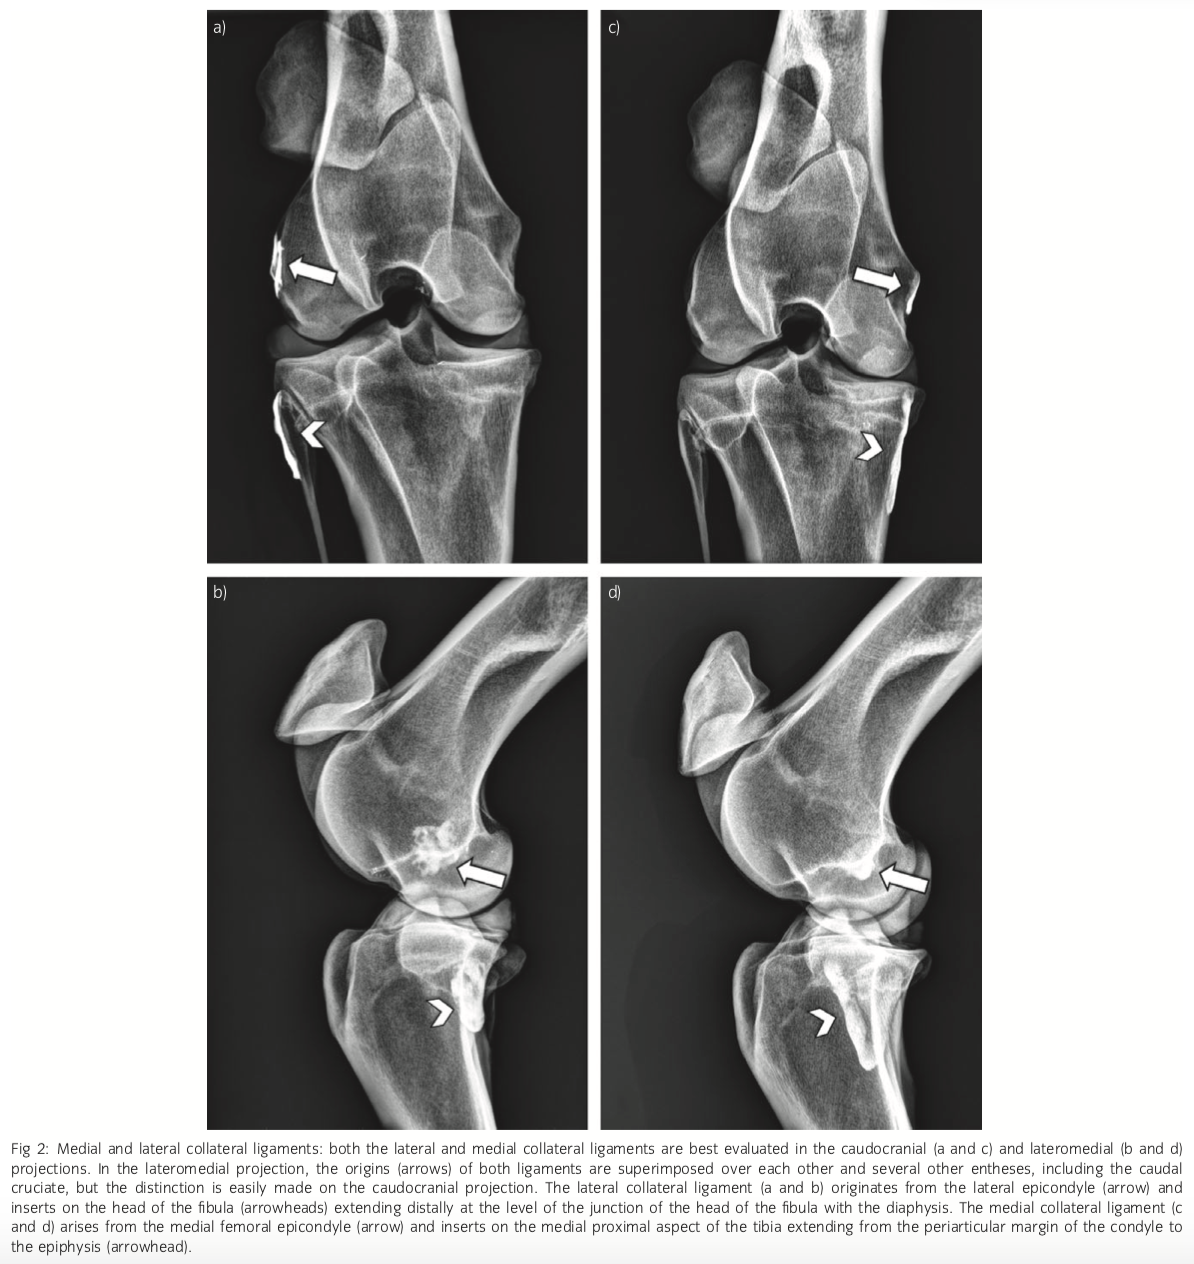

Collateral ligament origins and insertions

Medial and lateral femoral epicondyles

Medial inserts on medial tibial condyle extending into metaphyseal region

Lateral inserts on fibular head